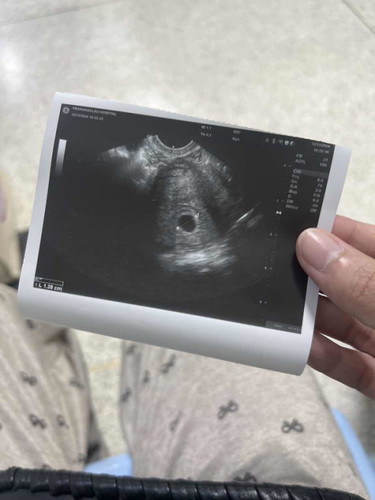

อายุครรภ์ 6 สัปดาห์ 3 วัน นับตามประจำเดือน เจอถุงตั้งครรภ์แต่ไม่เจอตัวอ่อน แบบนี้ปกติมั้ยคะ ตอนนี้แม่เครียดมาก 🥹 ขอคำแนะนำเพิ่มเติมทีค่ะแบบนี้จะมีลูกอยู่มั้ยคะ หมอบอกว่าตำแหน่งของถุงตั้งครรภ์อยู่ในตำแหน่งที่ปกติ แต่แม่ไม่เจอน้องเลย แบบนี้จะเป็นท้องลมได้รึป่าวคะ 🥲 หมอนับอายุครรภ์คลาดเคลื่อนไปเป็นไปได้มั้ยคะ แต่ไปซาวน์มาถุงครรภ์ดูโตขึ้นค่ะ ตอนนี้ได้ 1.28 cm ก็เลยไม่รู้ ว่าสรุปอายุครรภ์เท่าไหร่ กังวลไปหมดเลยค่ะตอนนี้ 😂

อ่านเพิ่มเติมค่ะแม่เราก็ยัง งง ถุงตั้งครรภ์เราตอนนี้แค่ 1.28 cm ค่ะเหมือนพึ่งมาเลยค่ะแม่ 🥹 รู้สึกว่าเล็กมากเหมือนอายุครรภ์น้อยกว่าที่หมอนับตามรอบเดือนขาด